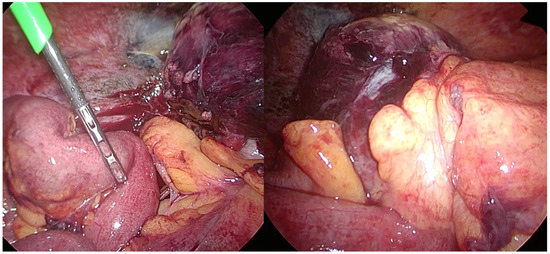

During the laparoscopy, the cecum was found to be dilated and discoloured (Figure 2).

Figure 2.

Laparoscopically, the cecum was found to be dilated with ischemic change, while the ileum and appendix were intact.